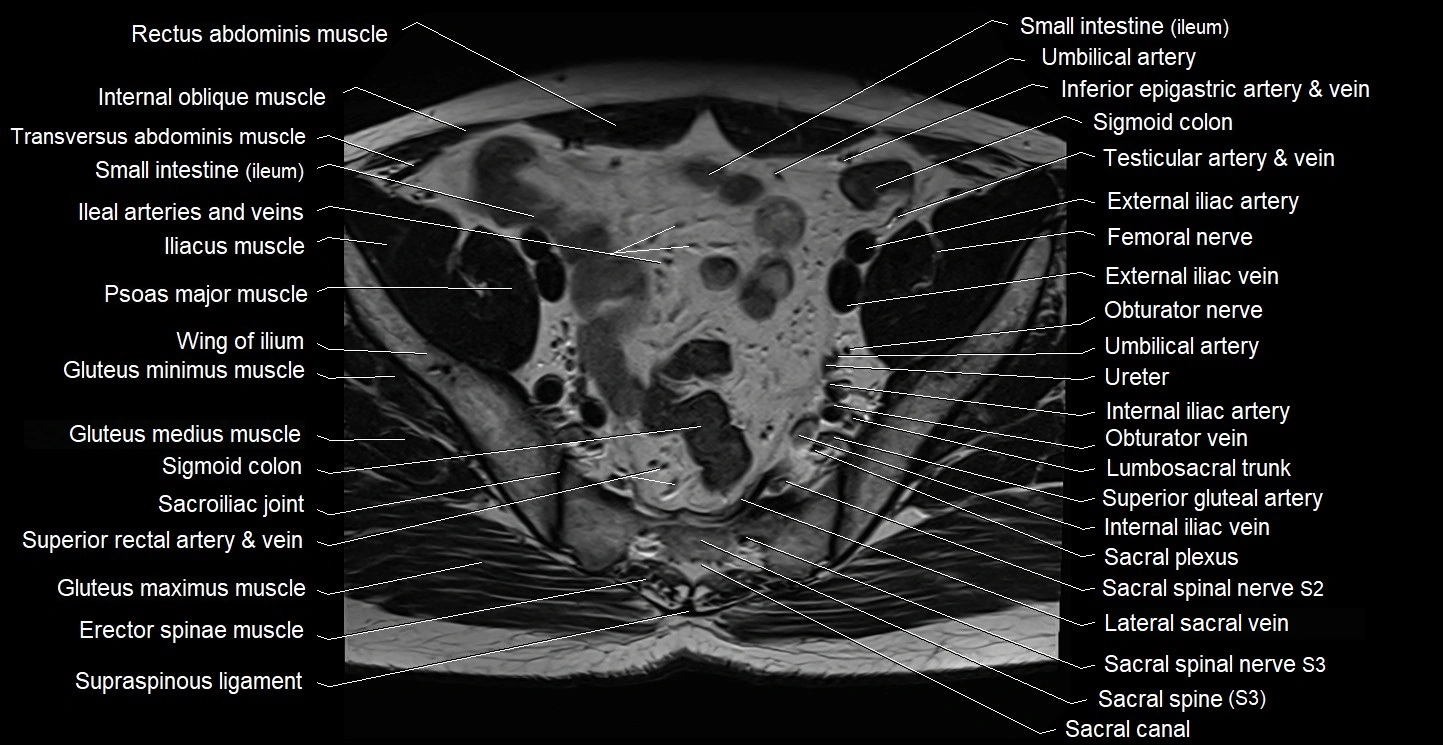

- Erector spinae muscles

- External iliac artery

- External iliac vein

- Femoral nerve

- Gluteus maximus muscle

- Gluteus medius muscle

- Gluteus minimus muscle

- Internal iliac artery

- Internal iliac vein

- Internal oblique muscle

- Lateral sacral vein

- Lumbosacral trunk

- Obturator nerve

- Psoas major muscle

- Sacral canal

- Sacral plexus

- Sacroiliac joint

- Sigmoid colon

- Spinal nerve S2

- Spinal nerve S3

- Superior gluteal artery

- Transversus abdominis muscle

- Umbilical artery